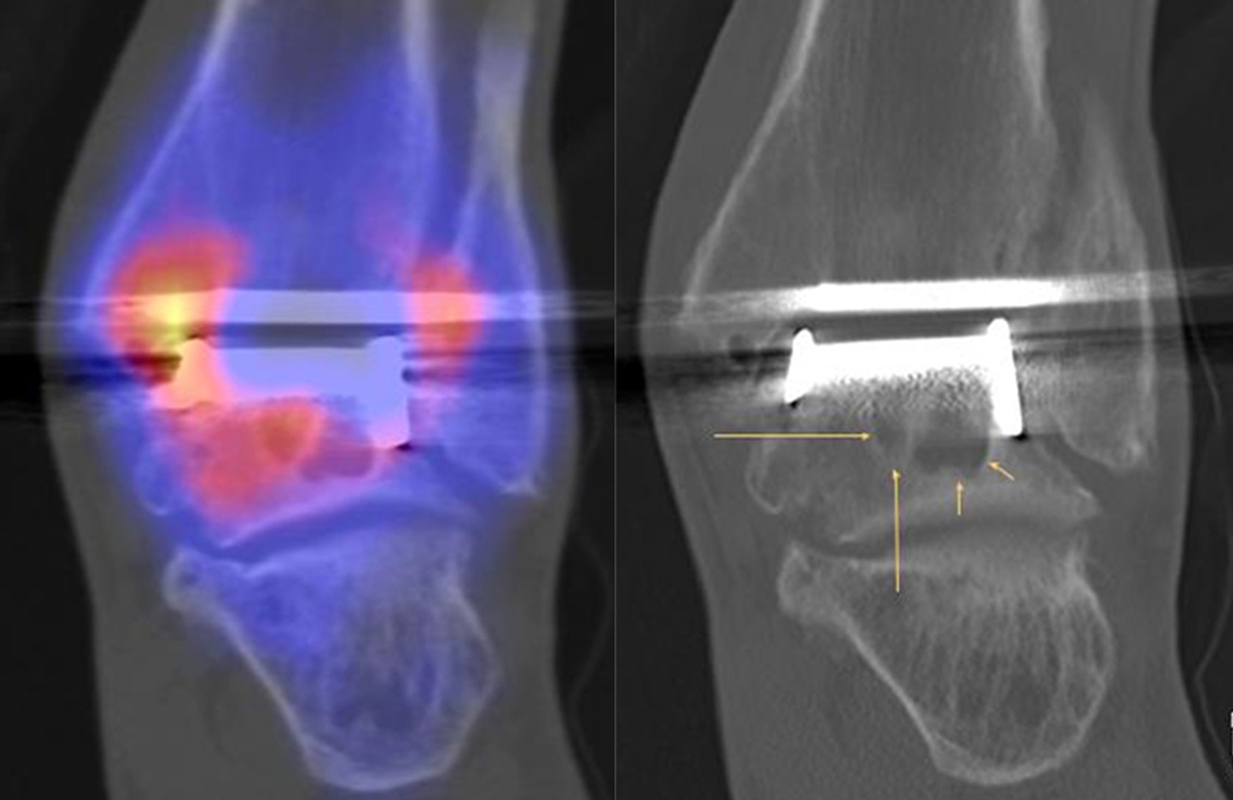

Beispiele für SPECT/CT-Untersuchungen nach OSG-TEP sind in den Abbildungen 6.1. bis 6.3. abgebildet.

Gurbani et al. evaluierten 37 Patienten mit schmerzhaften Sprunggelenkprothesen mit SPECT/CT und korrelierten die Ergebnisse mit klinischen und intraoperativen Befunden. Die SPECT/CT-Ergebnisse korrelierten zu 89,2 % (33/37 Pat.) mit der definitiven Diagnose. 28 Patienten wurden operativ revidiert und der Vergleich der SPECT/CT-Befunde mit den intraoperativen ergab eine Übereinstimmung von 92,9 % (26/28 Pat.). Die SPECT/CT identifizierte in den meisten Fällen aseptische Lockerungen (12/33 Pat.) und Impingement (11/33 Pat.). Seltenere Diagnosen waren Fehlstellungen (4/33 Pat.), Zystenbildungen (2/33 Pat.), subtalare Arthrosen (2/33 Pat.) und Infektionen (2/33 Pat.) 51.

Die Autoren beschreiben einen Fall, der neben einem Fokus am lateralen Malleolus auch eine starke flächige Anreicherung am talaren Prothesen-Knochen-Interface 17 Monate nach TEP-Implantation aufwies, so dass neben dem Verdacht auf ein laterales Impingement auch der Verdacht auf eine Lockerung der talaren Prothesenkomponente geäußert wurde. Intraoperativ bestätigte sich die Lockerung der talaren Prothesenkomponente nicht, sondern nur das laterale Impingement, welches mittels Debridement erfolgreich therapiert wurde 51. Da der Pat. bereits vor der TEP-Implantation eine Triple-Arthrodese erhalten hatte (welche im SPECT/CT unauffällig war), kann eine solche flächige Mehrspeicherung auch als weitgehend asymptomatische Stressreaktion gewertet werden.

Mertens et al. 52 berichten unter Anwendung eines standardisierten Auswerte-Schemas über eine Treffsicherheit von 96 % (Sensitivität 100 %, Spezifität 80 %) des SPECT/CT zur Diagnose der Ursachen für eine schmerzhafte Sprunggelenkprothese (n=24). Der SPECT/CT-Befund führte in 86 % zu einer spezifischen Therapie, welche in 83 % der Fälle zum Therapieerfolg führte.

Eine Analyse von Mason et al. 53 von 14 Patienten mit schmerzhaften Sprunggelenksprothesen, welche mittels SPECT/CT untersucht wurden, fanden in 13/14 Patienten ein SPECT/CT-Korrelat für die Beschwerden, wobei bei 12 Patienten der Fokus talar medial lokalisiert war. 8 Patienten wurden operativ revidiert und der Fokus entsprach einer verminderten bzw. fehlenden ossären Integration der talaren Prothesen-Komponente.